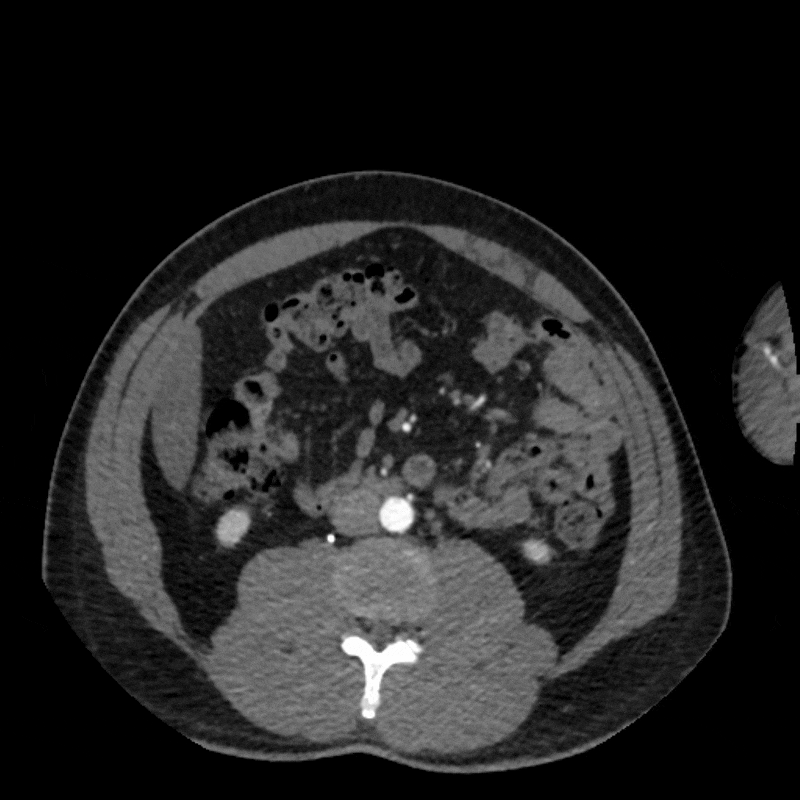

Figure C: Axial CT in a stressed position.

A dynamic CTA was performed in both relaxed and stressed (flexed) positions to simulate the limb posture during activity. Changes in hip and pelvic motion can alter the course of the external iliac artery, and narrowing that affects blood flow may appear only when the limb is under tension. Imaging at rest alone may overlook these positional changes, so evaluating both postures helps determine whether the symptoms are related to dynamic vessel deformation rather than fixed structural disease. (Learn about a similar condition, popliteal entrapment, here).

When the patient moved into the stressed position, the right external iliac artery showed two areas of luminal narrowing (a temporary decrease in the size of the vessel’s opening). One narrowing was more proximal (closer to the vessel’s origin near the pelvis) at about ten to twenty percent, and the second was more distal (farther along the vessel toward the leg) at about thirty to forty percent. Both returned to a widely patent appearance (fully open) when the leg moved back to a relaxed position.

The left external iliac artery remained patent across positions, and the common iliac arteries were tortuous (naturally curving) without any fixed stenosis. This pattern aligns with external iliac endofibrosis, where motion causes the artery to change shape rather than a fixed obstruction, highlighting why positional imaging can reveal abnormalities that may not appear on routine resting studies.